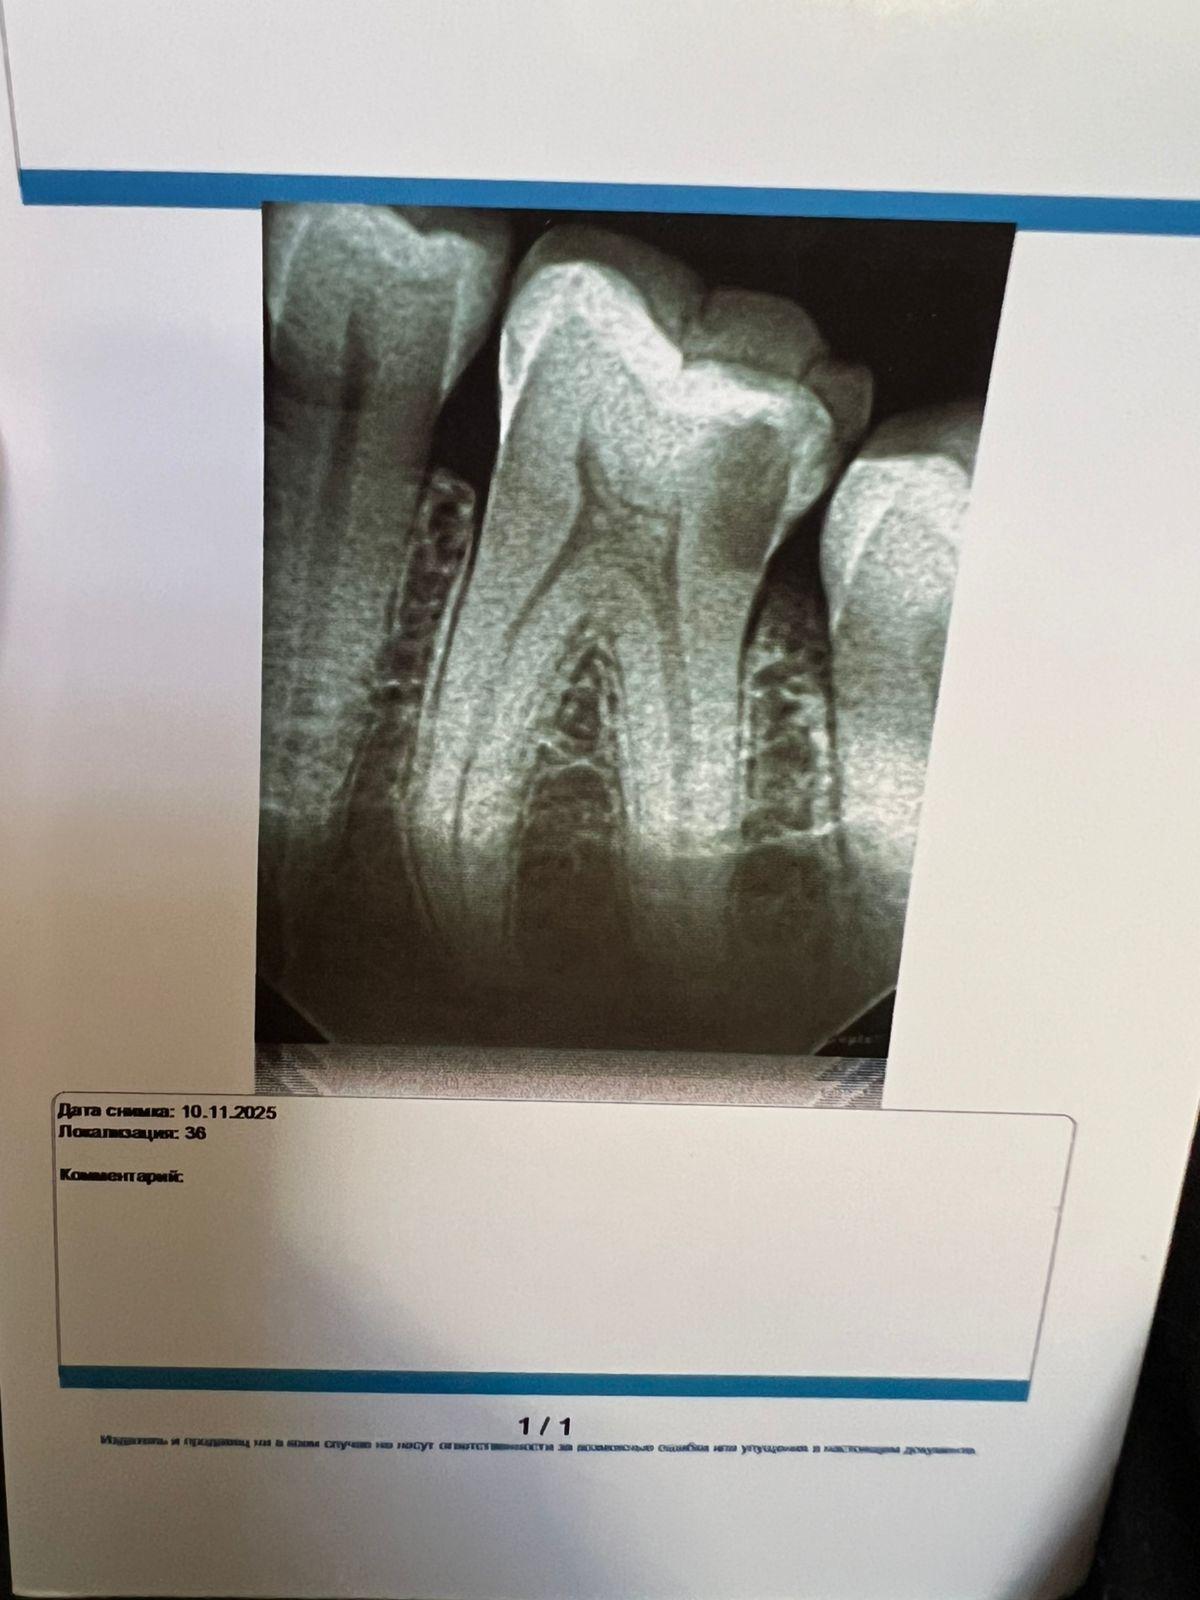

Здравствуйте, часто 15 зуб ноет, 1,5 года назад был вылечен ,удаляли нервы и запломбировали , на снимке где маленький кружок это пустота или пломба? И что это за потемнение на вверху где 16 зуб , была на приеме 10.11, сказали визуально зубы здоровые .И второй снимок 36 зуб , можно его вылечить без удаление нервов ?

по 36 - можно попробовать. Очень аккуратно чистить полость. Но, 100% ни один доктор не даст. Необходимо смотреть в процессе препарирования